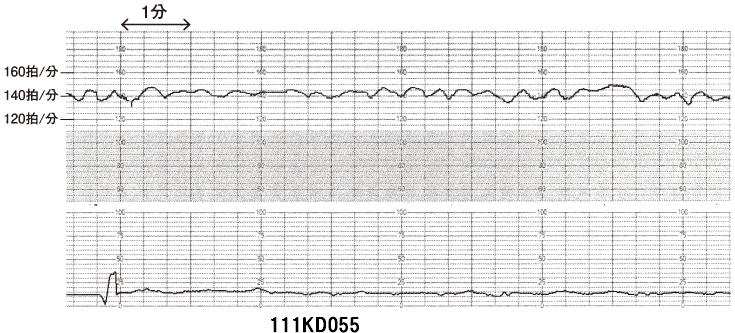

111D55血液型不適合妊娠 国試テコプラ。

好きです: 7